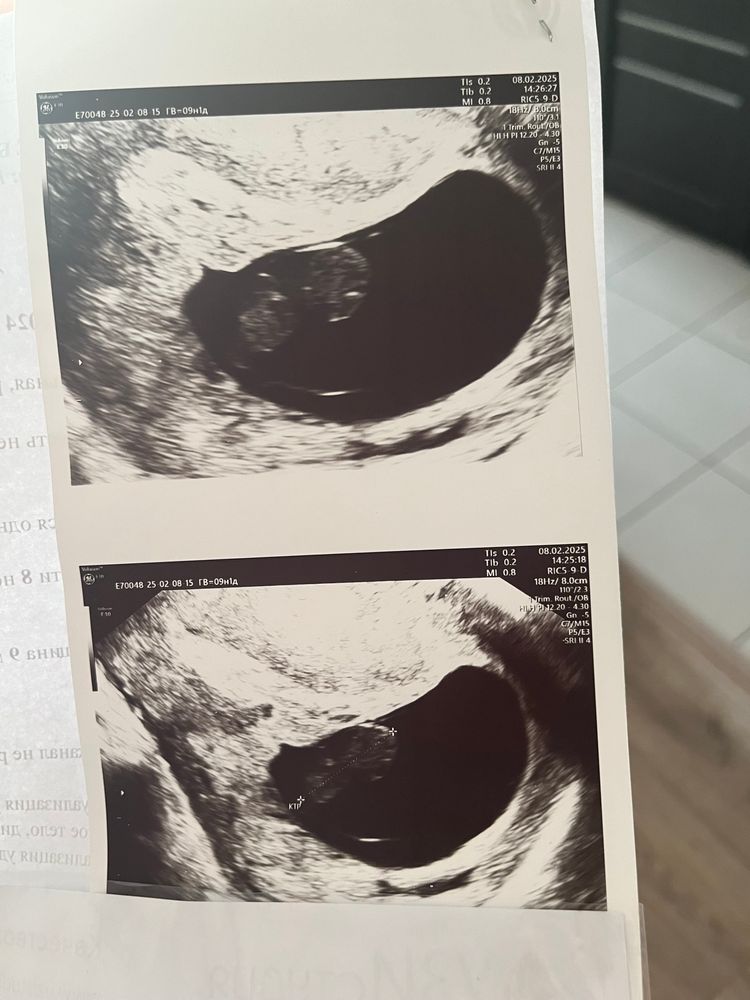

Замершая беременность

Девочки, подскажите возможно ли ошибка узи

срок по мес 9+1

2 недели назад была на узи, все отлично, сердцебиение 160

Ошибки бывают когда ранний срок и ктр маленький,а у вас ктр 20 мм с таким уже ошибка невозможна,это большой эмбрион,у меня ктр 18 мм так мне вообще через живот смотрели и были видны движения и ЧСС 180 был, сочувствую,но не хочу обнадеживать это замершая и недавно,так как эмбрион на 8,5 а у вас 9,1 получается буквально 3 дня назад замер(

Алина милая, это не тот пример,у автора эмбрион на 8,5 недель 20 мм у него руки и ноги уже есть, сердцебиение не услышать не возможно,это не ранний срок когда ктр 3-5 мм и сложно уловить и 2 недели назад с маленьм эмбрионом сб было,а с большим уже нет

Не заметить сердцебиение не возможно, увы. На таком сроке даже глазами видно как сердечко бьется.